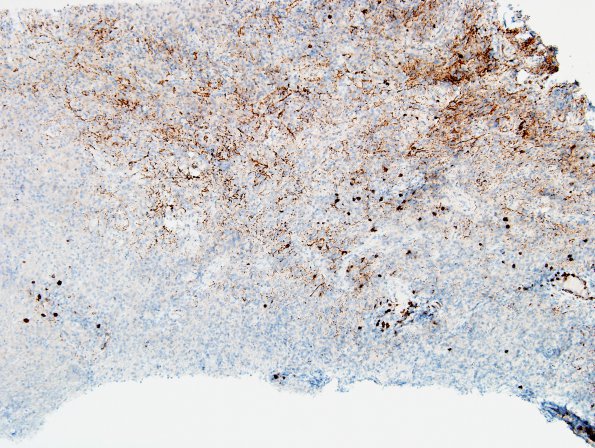

Washington University Experience | MYELIN (IMMUNE-MEDIATED) | Sentinel & Steroid Rx Lesions | 2G1 Sentinel Lesion (Case 2 - 1st Bx) area B CD20 10X 2

2G1-4 Variable numbers of CD20 containing B cells are scattered throughout the lesion but are typically outnumbered by T cells and some areas are nearly devoid of B cells (CD20 IHC)